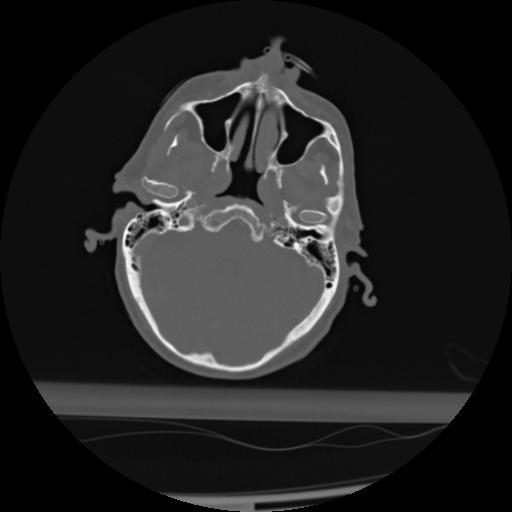

21 ANGIO,CE,Axial,3.0,ANGIO,,